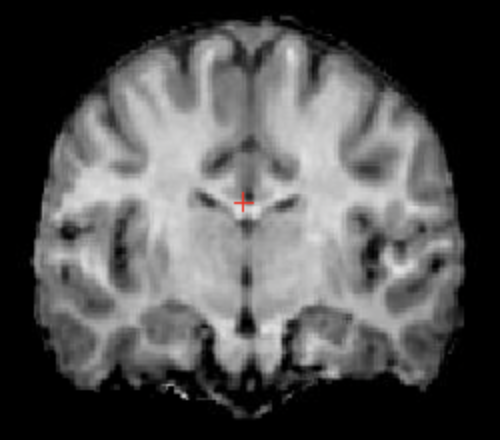

Here, we use both the INU model described in Equation 7 and the homogeneous noise model described in Equation 8. For the former, we use random fields with increasing spatial frequency (). We denote the corresponding learnable parameters , and , with preset values . Noise-free target “real”, and learned images are shown in Figure 2. Inference results for the value of the noise parameter are reported in Table 3, and are in line with those obtained in the noise-only experiment.

| (a) Noise-free image | (b) Learned image | (c) Real image |